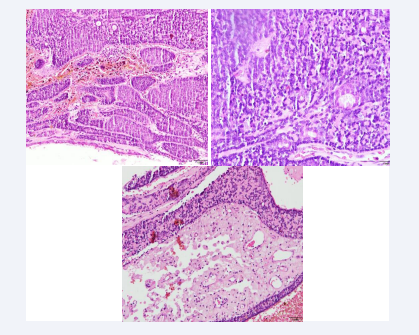

Figure 1: The sections show atrophic skin with loss of the ridge network that surrounds a neoformation consisting of two different histological patterns. The first and predominant one is composed of a multinodular proliferation composed of small cells with round and hyperchromatic nuclei and larger cells with clear cytoplasm, vesicular nucleus and prominent eosinophilic nucleolus, which are arranged in a trabecular pattern, with foci of ductal differentiation. presence of hyaline droplets and predominantly lymphocytic inflammatory infiltrate. Courtesy: Dr. Mónica Salazar- Dermatopathologist

Figure 2: A second pattern is composed of islands of basaloid cells that have a puzzle-shaped arrangement and are surrounded by a thickened eosinophilic basement membrane. In addition, prominent cystic changes are observed that compromise the spiradenomatous part of the lesion and are associated with intratumoral hemorrhage. Courtesy: Dr. Mónica Salazar- Dermatopathologist

Figure 3: During the year 2021, multiple giant spiroadenocylindromas are observed, the largest diameter being located in the parieto-occipital region, causing aesthetic deformation of the skull. During the year 2023, the excision of several tumors has been achieved in 5 stages of minor surgery, allowing the skin to expand and recover.